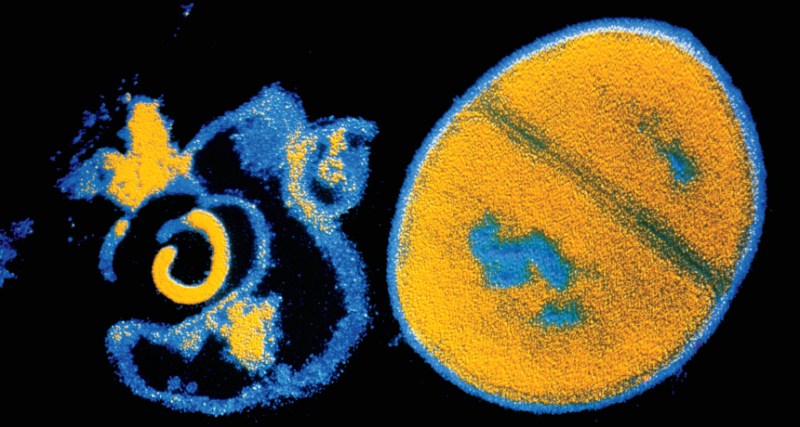

9. Life

With Taxol, chromosomes divide and get conquered

New mechanism discovered for how the cancer drug Taxol works.

By